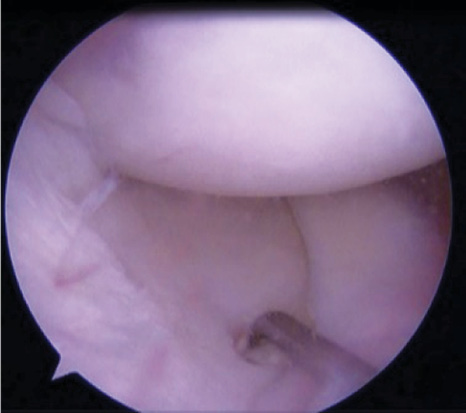

During the revision of ACL reconstruction, in 1 (1.1%) case, the location of the tibial channel was near the anterior horn of the internal meniscus (Figs. 4, 5).

Fig. 4. Location of the tibial canal near the anterior horn of the meniscus.

Fig. 5. Channel layout.